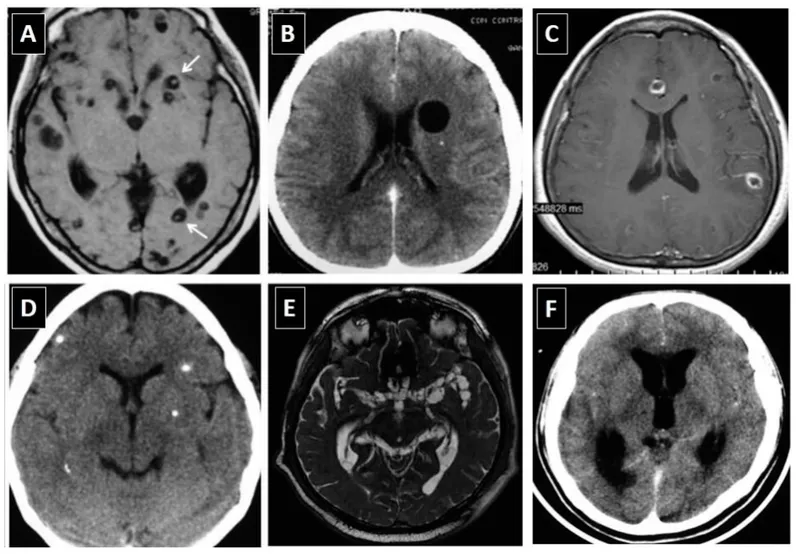

- Neurocysticercosis (NCC): Commonest cause of adult-onset seizures in endemic areas.

- Dx: CT/MRI (calcified granulomas, vesicular cysts with scolex). Rx (NCC): Albendazole + Corticosteroids.